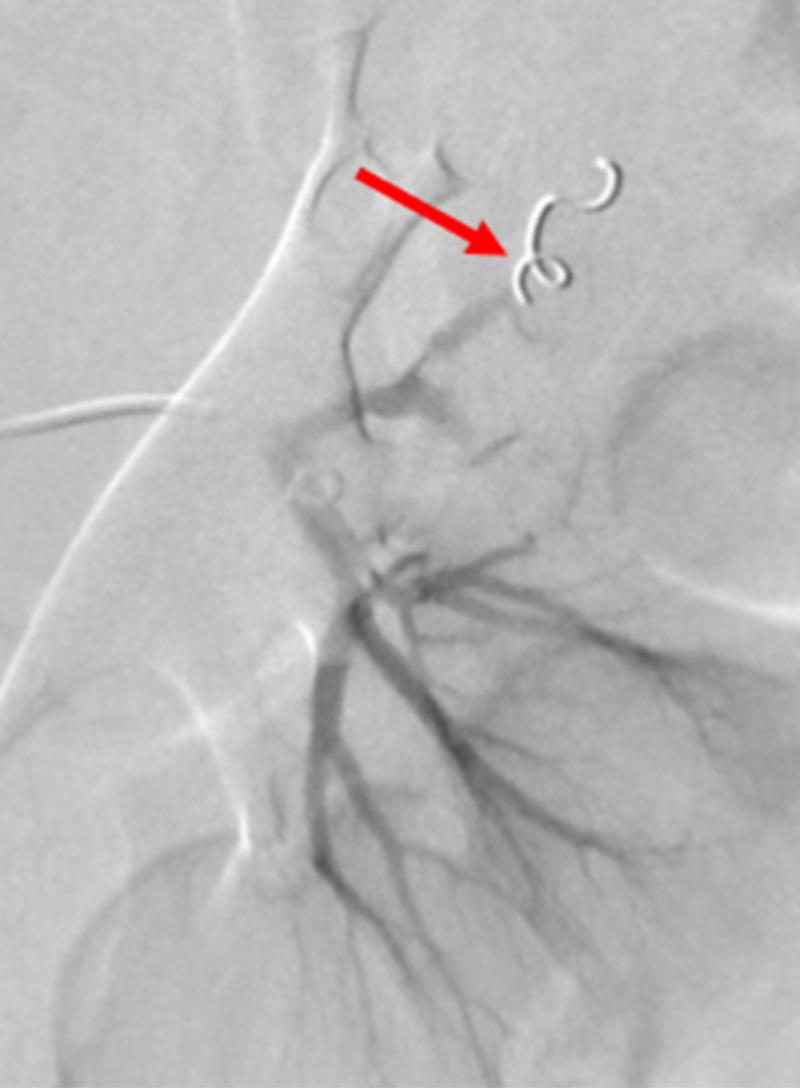

The use of traditionally available intra-arterial devices have historically been designed with the adult patient population in mind. Currently, there are not manufactured devices specifically tailored for use during pediatric interventional procedures, pressuring interventional operators to adapt commonplace and readily available devices for interventional management. Experienced interventional operators understand that pediatric and adult interventions can entail vastly different management, affecting patient care and outcomes. To address the pitfalls in pediatric interventional management, an accredited fellowship specifically for pediatric interventional radiology is available. However, devices must equally evolve with the training available in order to adequately address interventional management of the pediatric patient population. Interventional device innovation can be considered the initial step towards bridging the technical and procedural gaps necessary for refining pediatric intervention. The introduction of steerable microcatheters in interventional radiology has innovated procedural protocols, but has never been documented in pediatric patients until this time.

传统可用的动脉内装置在设计时历来考虑的是成年患者群体。目前,尚无专门为儿科介入手术设计制造的装置,这迫使介入手术操作人员采用常见且容易获得的装置进行介入治疗。经验丰富的介入手术操作人员明白,儿科和成人介入手术在管理上可能有很大差异,会影响患者护理和治疗结果。为解决儿科介入治疗管理中的缺陷,现有专门针对儿科介入放射学的认可进修项目。然而,装置必须与现有的培训同步发展,以便充分应对儿科患者群体的介入治疗管理。介入装置创新可被视为弥合完善儿科介入治疗所需的技术和程序差距的第一步。可操控微导管在介入放射学中的引入革新了手术方案,但在此之前从未有过在儿科患者中的相关记录。